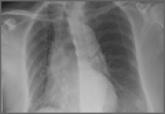

Emergency Imaging: Multiple Comorbidities With Fever and Nonproductive Cough

- Author:

- J. Jacob Kazam, MD

- Steven Daniels, MD

- Jessica Fisher, MD

- Edward Ebani, MD

- Keith D. Hentel, MD, MS